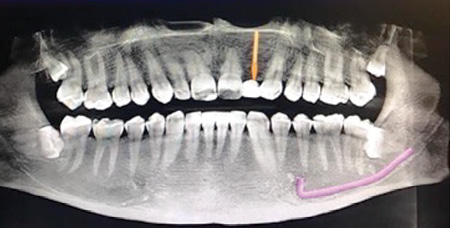

A 32-year-old male presented with a congenitally missing lateral, No. 10. The buccal-lingual dimensions were sufficient for standard implant placement, but the mesial-distal dimensions were 4.56 mm (figures 1a and 1b). The patient had a failing Maryland bridge, both functionally and esthetically (figure 2). He was always told that implants were not an option for him unless he underwent significant orthodontic treatment, and even then, nothing was guaranteed.

Figure 1a: Pre-op panorex

Figure 1b: Pre-op CT scan

Figure 5: Post-op panorex

A 50-year-old female presented with a missing tooth No. 12 that was extracted for unknown reasons more than 10 years ago (figure 7). The patient was referred to our office for an implant consultation. Upon review of a CT scan, it was revealed that at the widest area buccal-lingually there was 4.09 mm and at the narrowest 3.8 mm (figure 8). She was presented with two treatment options: bone grafting or a narrow-diameter implant. She opted for the narrow-diameter implant, as it eased several of her concerns: she was unhappy with a removable appliance, worried about a block graft for a single tooth, and finances were a burden.

Figure 7: Pre-op panorex

Figure 8: Pre-op CT scan

A 1.8 mm x 14 mm Anew implant (Dentatus) was selected, and a surgical guide was fabricated for a flapless approach. In this instance, a healing cap was placed, and the existing flipper was relieved to address financial concerns (figures 9 and 10). A screw-retained crown was fabricated three months post insertion (figures 11 and 12). The patient reported no postoperative discomfort, and the case remains successful, as shown in the two-year postoperative x-ray (figure 13).

Figure 13: Two-year follow-up